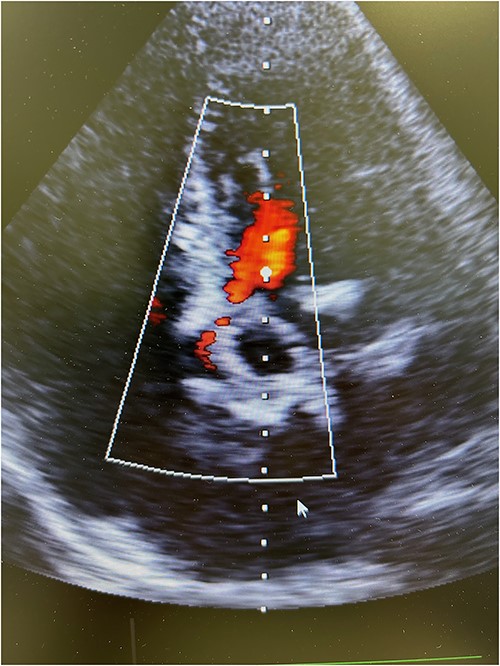

Resternotomy was undertaken and the aortic root was dissected free of considerable adhesions. The aortic arch and the remnant of the right atrial appendix were cannulated to initiate cardiopulmonary bypass and retrograde cardioplegia was administered after cross-clamping of the aortic prosthesis, which was thereafter transected immediately distally to the previous proximal aortic suture line. Care was applied while the destroyed aortic valve prosthesis and the coronary ostia were dissected free from the left outflow track encompassing the calcified annular structure, pledgets, and suture material. Though the aortic root remained intact after surgical revision, the remnant aortic valve annulus was torn and an intramyocardial defect was evident beneath the left and right coronary ostia. A size 23 mm rapid-deployment Edwards Intuity bioprosthesis was implanted with the aid of three guiding sutures that also ensured the integrity of the coronary ostia. The skirt of the prosthesis was raised up and the aortic valve prosthesis was well fit despite the revision lesions and intramyocardial calcium of the left outflow track beneath the old aortic valve annulus. After surgical closure of the supracoronary aortic prosthesis and weaning from cardiopulmonary bypass, echocardiography revealed a well-seated aortic valve prosthesis with a trace of paravalvular leak (Fig. 3). The patient experienced minimal weakness of the left arm during an otherwise uneventful recovery without cerebral lesions observed by computed tomography. Clopidrogel was readministered and the patient was dehospitalized after 10 days of surgery.

Postoperative transesophageal echocardiography showing nonsignificant regurgitation of a well-seated rapid-deployment Edwards Intuity bioprosthesis.